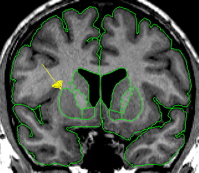

|  | The putamen is a subdivision of the lenticular nucleus (the other division is the pallidum). The lenticular nucleus from the axial view resembles a rounded triangle that is divided into two major sections. The putamen is the lateral part of this triangle.The putamen starts small and ends small in the coronal view. The putamen quickly grows to its greatest size in the middle and in the medial posterior portion it closely resembles a goldfish shape. The putamen lies lateral and partially anterior to the thalamus. It is bordered laterally, superiorly, and inferiorly by white matter. The putamen is usually bordered medially by the pallidum. When the pallidum is not yet present or has already disappeared the putamen is bordered medially by the internal capsule. | |

It is important not to include the claustrum in the putamen; this is the strip of tissue bordering the lateral edge of the putamen. Often the putamen can be extracted at the same time as the caudate especially in the area where they are connected by the nucleus accumbens. The histogram of the caudate, in many cases, is close to what you want for the putamen as well. After extracting the caudate, before deleting the remaining red lines, you can often go immediately into the intensity contour function and adjust them to fit the putamen.  This should be done separately for each hemisphere. | ||

| Part II - Blood vessels There is often a blood vessel near the inferior border of the putamen, this should not be included as part of putamen. The vessel should be extracted separately using a contour line and labeled "vessel." The vessel will serve as at least a portion of the inferior border. | ||